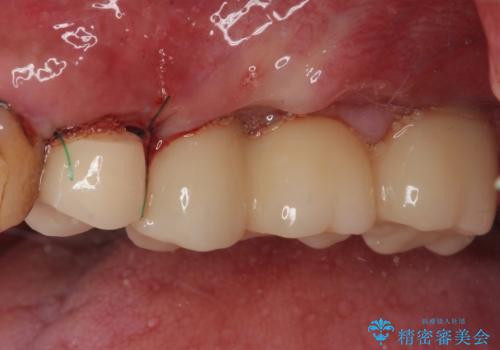

割れてしまった奥歯 抜歯即時埋入インプラントによる短期間治療

- 土台の歯が割れてしまって、歯がグラグラしているとのことで来院された患者様です。

いずれの歯も抜歯が必要な状態であり、抜歯即時埋入によるインプラント治療を行うこととしました。

右上奥歯は骨欠損の範囲が広いため、抜歯即時埋入は可能であっても、即日で仮歯を装着する即時荷重は難しいと判断されたため、手前の歯まで仮歯を装着することとしました。

術後にインプラントの安定値を測定し、十分な値が達成された後、速やかにセラミッククラウンにて補綴治療を行うこととしました。

強い咬合力により歯根破折を繰り返しているため、即日荷重あるいは早期荷重による他の歯への負担を軽減することが重要となります。

抜歯即時埋入インプラントは、咬合力によるトラブルを回避する、非常に有用な手段となります。